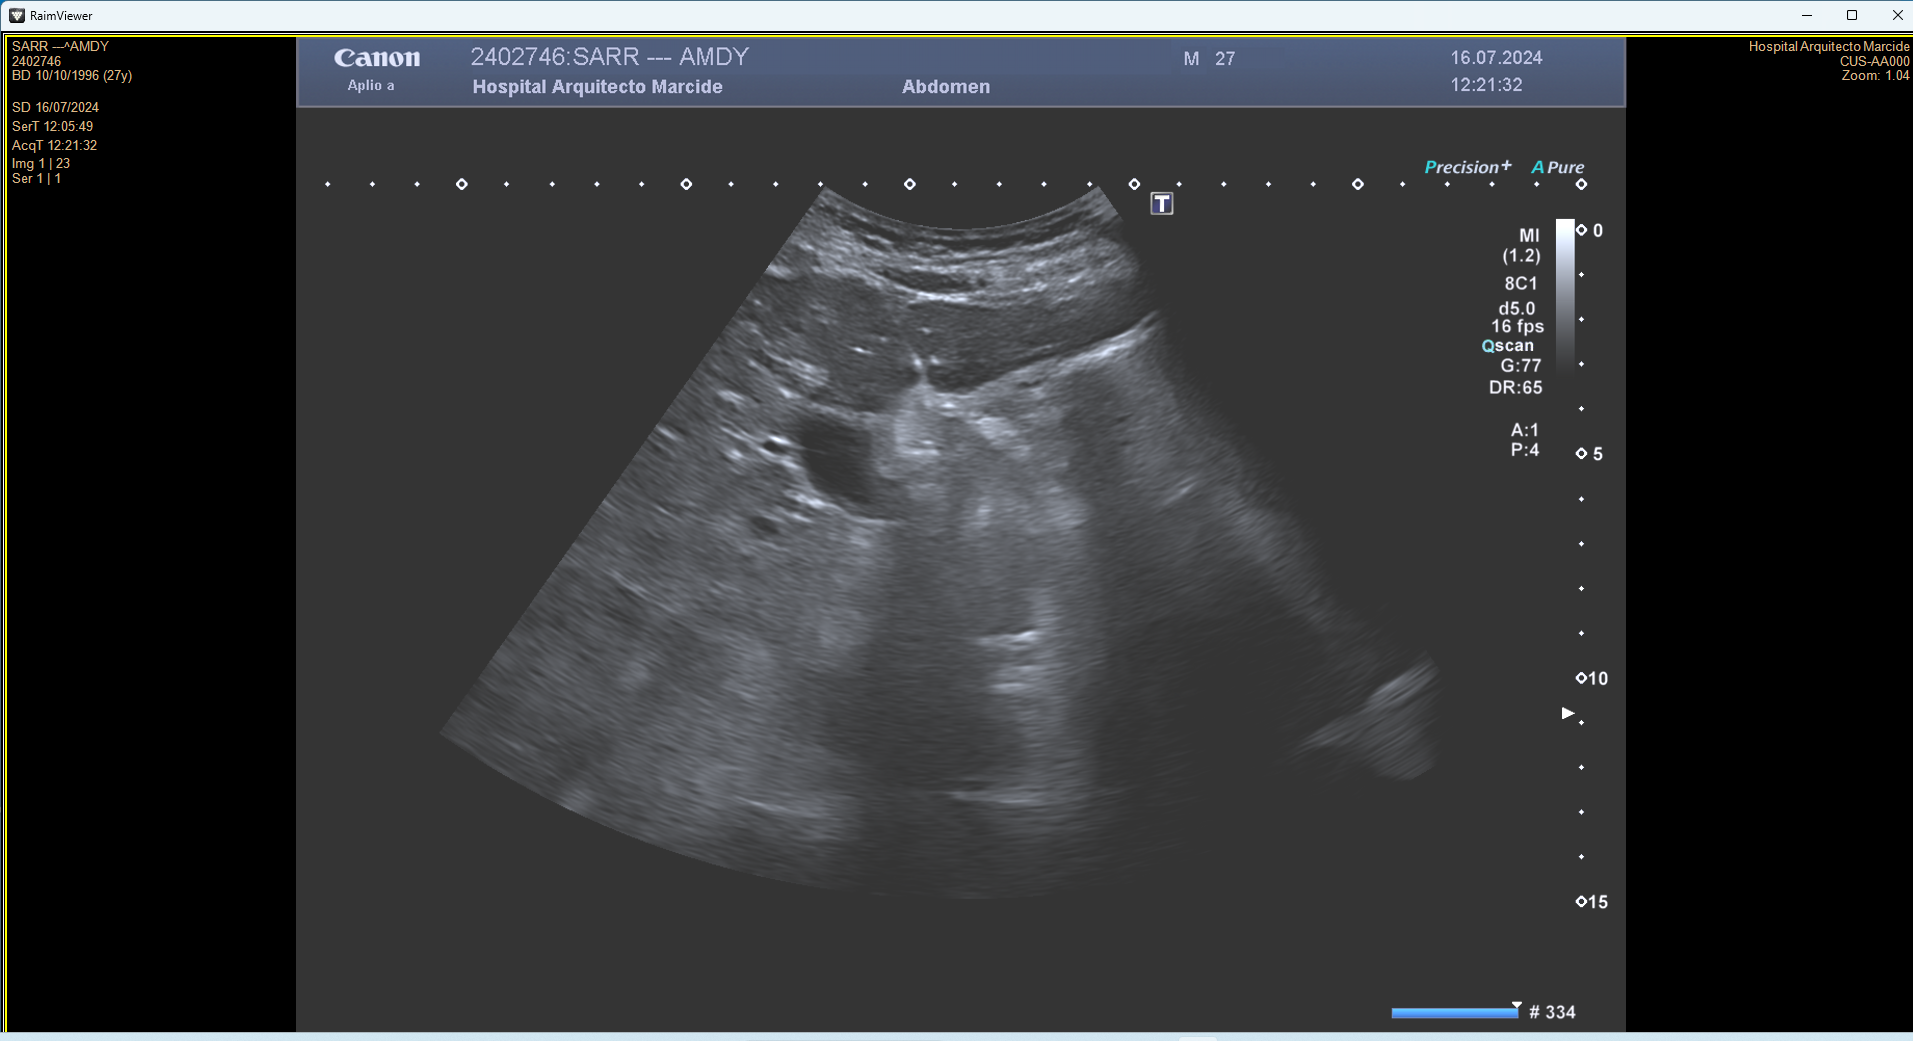

Descripción de los hallazgos ecográficos y las imágenes más relevantes para la resolución del caso

En ecografía en Centro de Salud: La práctica totalidad del parénquima hepático se encuentra sustituida por múltiples lesiones sólidas nodulares hiperecoicas, de predominio en el lóbulo hepático derecho, donde presentan tendencia a la confluencia y conforman una masa que alcanza los 13 cm de diámetro máximo. La vena porta es permeable y ectásica, con esplenomegalia. Ambos son signos de hipertensión portal.

Ante estos hallazgos se deriva al paciente a Urgencias.